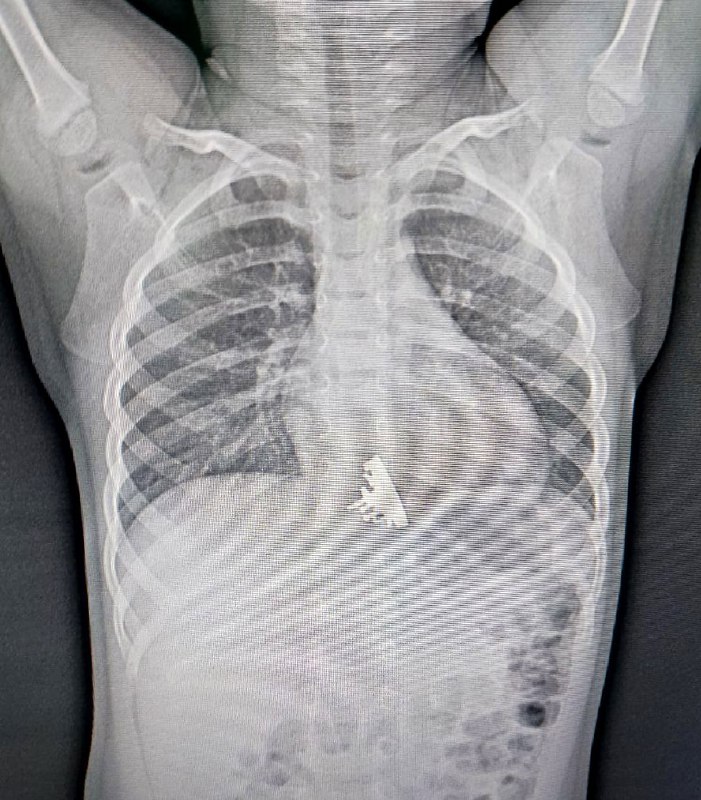

Малышка играла с конструктором и в момент неосторожности проглотила предмет. Родители заметили, что дочка поперхнулась, начала подкашливать и обратились в приемное отделение ОГАУЗ ГИМДКБ. Рентгеновский снимок подтвердил наличие инородного тела в нижней трети пищевода. Было решено немедленно провести эзофагогастродуоденоскопию.

Фото Ивано-Матренинской детской клинической больницы

Врач отделения эндоскопии Илья Пикало отметил, что опасность заключалась в наличии острых выступающих частей на инородном теле, которые могли повредить стенки пищевода, за что они цеплялись. По этой причине извлечение «Авроры» заняло значительно больше времени, нежели это потребовалось бы для удаления обычной монеты, к примеру.